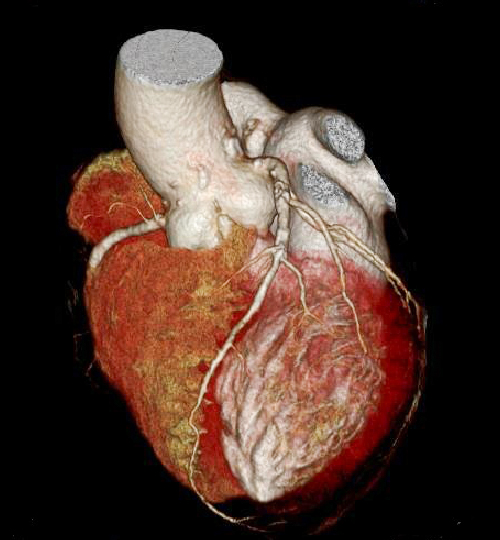

320列CT装置(Aquilion ONE)

最新型320列CT装置で、従来型の64列CT装置に比べて、より精密な検査を短時間で受けることができます。

- 心臓CT撮影が、より簡単に、より低被ばくに行えるようになります。 検出器の列数が一般的に使用されている64列CTの5倍、320列のCTです。 心臓は1心拍分だけの短時間で撮影できるので、検査はすぐに終了します。 1心拍分のスキャンで心臓全体を撮影できるので、従来装置では難しかった不整脈の場合の撮影でも、殆どの場合は問題なくスキャンできます。 最新機種なので、心臓の拍動によるブレをAI(人工知能)技術で修正する機能も搭載しています。また、造影剤もより少ない量で撮影できるので、心臓CT検査のハードルが従来の装置よりもかなり低くなり、どなたでも気楽に検査を受けていただけます。